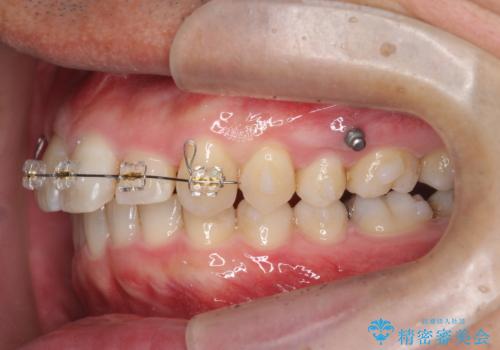

2級ディープバイト 遠心移動を伴うマウスピース矯正

・深い噛み合わせ(ディープバイト) ・2級性の咬合関係(上顎前突)・前歯のがたつき

以上のような歯並びの問題をマウスピース矯正インビザライン・カリエール・マイクロインプラント・部分ワイヤー矯正

を用いて改善していきます。

深い噛み合わせと上顎前突の状態を治すのに時間がかかりましたが、治療後は理想的で安定した咬合関係となりました。